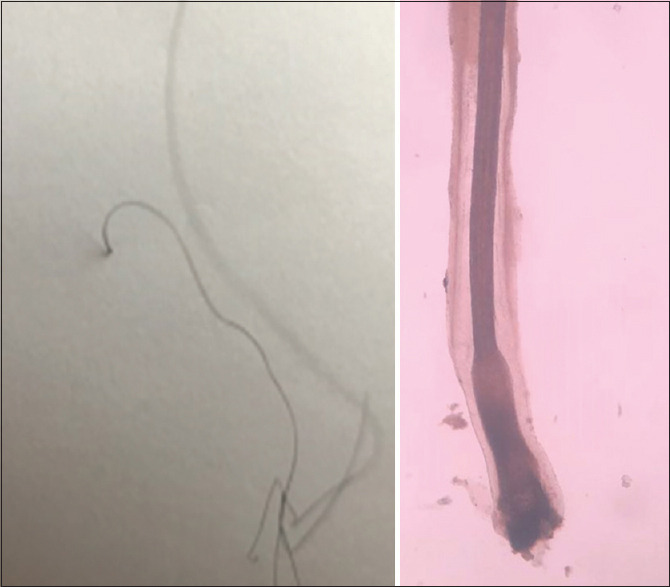

Patients and methods: In a prospective study, during 2 years, 83 treated LPP patients have been divided into two groups of 41 and 42. Group 1 instructed for paper sign test which is to comb their hair over a white paper sheet to catch any fallen hairs, then turn the paper upside down, if all collected hair on paper completely separated, test is considered negative, if even one hair hangs onto the paper, the test is considered positive. Group 2 trained for clinical symptoms (hair shedding, scaling, itching, pain, tenderness, and burning).

Results: From the first group, 13 patients had positive paper sign, and from the second group, 35 patients had clinical symptoms; after clinical examination and biopsy, 13 from Group 1 and 17 from Group 2 were confirmed to have reactivated disease. Patients in the first group who had been trained for paper sign test became aware of relapse sooner and came earlier for the evaluation of disease.